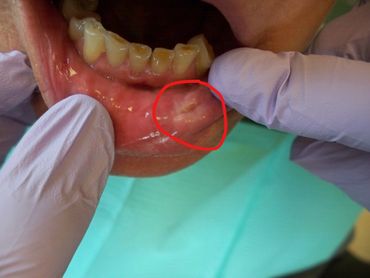

Bridge placed. A bridge is a permanent addition to the mouth that functions like a natural tooth